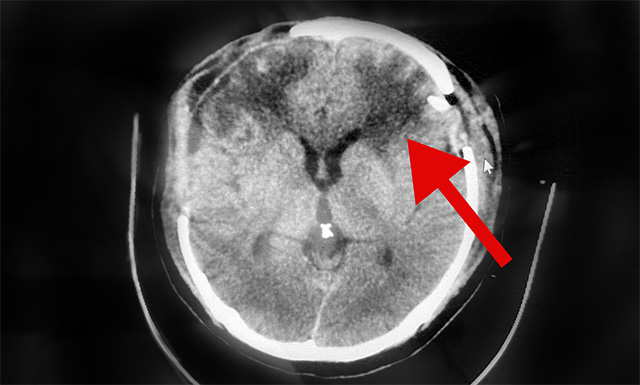

10月4日,經(jīng)與神經(jīng)外科6A病區(qū)侯增欣主任會(huì)診后認(rèn)為,患者趙先生右側(cè)硬腦膜下血腫雖已清除,但CT檢查顯示其左側(cè)硬腦膜下仍存在較大面積血腫,顱內(nèi)壓高,非常危險(xiǎn)隨時(shí)形成腦疝,必須馬上手術(shù)。

▲術(shù)后CT示:患者左側(cè)腦內(nèi)血腫已清除